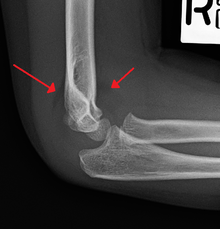

An elbow X-ray showing a displaced supracondylar fracture in a young child | |

Diagnosis is usually by x-ray. The fracture can however be difficult to identify and often a joint effusion is used to increase one's suspicion of the presence of a fracture. The existence of an effusion can be determined by the presence of the sail sign.

Upon examination the doctor will evaluate the arm for signs of damage to the nerves and blood vessels; they will look for swelling and deformity. This will allow the doctor to determine a likely diagnosis. Damage to the elbow is a common injury in children; injuries to blood supply of the arm may necessitate early surgical intervention.[4] Most of the supracondylar fractures are minor and require a period of rest, analgesia and compression prior to graduated formal rehabilitation.[5] In the event of a more severe injury, the fracture will be visible on an x-ray. It is important in diagnosis to understand the dynamics of an x-ray because growth plate fractures may not show up like normal broken bones. It is a good idea to compare the x-ray of the injured elbow to the opposing side for analysis.[4] If rest does not cause the fracture to heal then the child must be referred to a specialist for assessment of the injury.[5]